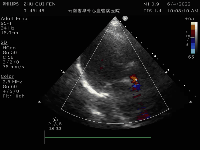

患者71岁老年女性,体重42kg,身高156cm,因突发活动后心累气紧合并心绞痛急诊入院,超声提示主动脉瓣膜重度狭窄,左心功能减低EF 46%,主动脉瓣峰值流速5.2m/s, 平均跨瓣压差68mmHg(图1),冠脉造影提示冠脉未见明显狭窄,患者合并COPD,TIA等并发症,STS评分>6分,经外科团队讨论提示传统外科高风险,经过多学科讨论拟行TAVR手术。术前CTA评价提示三叶式主动脉瓣(图2),Area 479.2mm²,Perimeter 77.9mm,Area折算瓣环直径24.7mm,左侧冠脉开口高度16.1mm,右侧冠脉开口高度16.5mm,瓣膜重度钙化,主要分布于瓣叶,LVOT无特殊,主动脉窦平均内径31mm,患者外周血管尚可无明显钙化扭曲,最细5.9mm(图3)。

图1:术前超声心动图提示主动脉重度狭窄